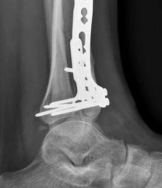

With the articular surface reconstituted, the surgeon's focus shifts to bridging the complex metaphyseal-diaphyseal dissociation. A pre-contoured anatomical locking plate is slid submuscularly or subcutaneously along the diaphysis using a MIPPO technique. The plate is positioned on the anterolateral or medial surface, depending on the preoperative plan and soft tissue constraints.

The distal portion of the plate is secured to the reconstructed articular block. It is imperative that the distal locking screws are placed parallel to the joint space, forming a rigid subchondral raft that supports the articular cartilage. Fluoroscopy is utilized extensively to ensure no screws have penetrated the joint. Once the distal block is secured to the plate, the diaphyseal segment is aligned. Length, alignment, and rotation are restored using manual traction or the femoral distractor. The proximal portion of the plate is then secured to the diaphysis using a combination of non-locking screws (to pull the bone to the plate) and locking screws (to create a fixed-angle construct). The working length of the plate is maximized by leaving several screw holes empty over the zone of comminution, promoting secondary bone healing.